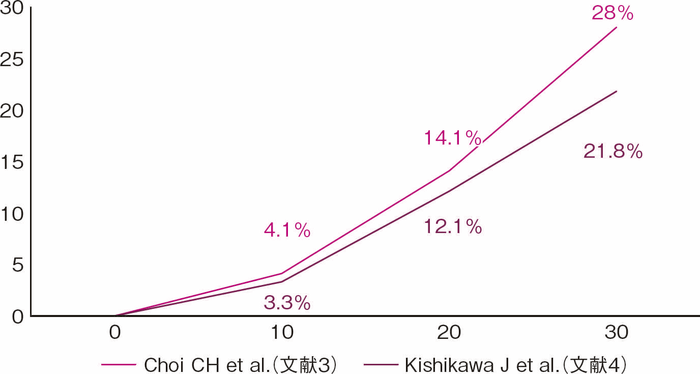

UCは長期罹患に伴う粘膜の慢性炎症を背景に発癌リスクが上がることが知られており,1925年にCrohnとRosenbergが最初のUC関連大腸癌の報告を行って以降,これまで多くの報告がなされてきた1)。UC関連大腸癌は罹患年数が長くなるにつれ発生リスクが上がるとされ,2001年Eadenらの報告では,浸潤癌の累積発生率は10年で1.8%,20年で8.3%,30年で18.4%であることが示された2)。一方近年では,英国Choiらの報告にて10年で0.1%,20年で2.9%,30年で6.7%とされ,罹患年数に伴う累積発生率は低い値を示している3)(図1)。本邦ではKishikawaらの報告によると,浸潤癌の累積発生率は10年で0.7%,20年で3.2%,30年で5.2%でありChoiらの結果同様であったが,一方でdysplasiaも含めた腫瘍性病変の累積発生率は10年で3.3%,20年で12.1%,30年で21.8%であり,依然長期経過での発生率は高く注意すべき問題である4)(図2)。また炎症の範囲が広いほど発癌リスクが上がることも知られており,Ekbomらの報告によると一般集団と比較した大腸癌発生の相対危険度は,直腸炎型では1.7倍,左側大腸炎型では2.8倍,全大腸炎型では14.8倍であり,広範囲の炎症を伴う場合にも注意を要する5)。

図2 大腸腫瘍累積発生率